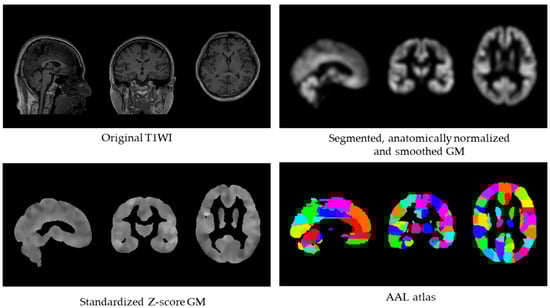

Core Body Temperature Negatively Correlates with Whole-Brain Gray Matter Volume: A Pilot Study in the Context of Global Warming

by

Keisuke Kokubun, Kiyotaka Nemoto, Yoshimitsu Yamamoto, Ayumu Mitera and Yoshinori Yamakawa

Brain Sci. 2025, 15(12), 1324; https://doi.org/10.3390/brainsci15121324 - 12 Dec 2025

Abstract

Global warming has been associated with various adverse effects on human physiology, yet its potential impact on brain structure remains largely unexplored. The present pilot study investigated the relationship between core body temperature and whole-brain gray matter volume (GMV) in healthy adults. Twenty-seven

[...] Read more.

Global warming has been associated with various adverse effects on human physiology, yet its potential impact on brain structure remains largely unexplored. The present pilot study investigated the relationship between core body temperature and whole-brain gray matter volume (GMV) in healthy adults. Twenty-seven participants (19 males, 8 females; mean age = 38.6 ± 10.3 years) underwent MRI scanning and core temperature assessment. Correlation and partial correlation analyses were performed to examine the association between core body temperature and GMV, controlling for demographic and physiological covariates summarized by the first principal component. Core body temperature showed a significant negative correlation with whole-brain GMV (r = −0.496, p = 0.009; 95% CI = −0.737 to −0.143) and a trend-level significant partial correlation after covariate adjustment (r = −0.373, p = 0.060; 95% CI = −0.660 to 0.008). These trends remained after correction for multiple comparisons using the Benjamini–Hochberg false discovery rate. Exploratory analyses across 116 AAL regions identified the left Fusiform gyrus as showing a significant negative correlation with core body temperature (r = −0.643, p < 0.001). Given the modest sample size, these findings should be interpreted cautiously as preliminary, hypothesis-generating evidence. They suggest that even subtle variations in body temperature within the normal physiological range may relate to differences in global brain structure. Possible mechanisms include heat-induced inflammation, oxidative stress, and increased metabolic load on neural tissue. Understanding how individual differences in body temperature relate to brain morphology may provide insights into the neural health consequences of rising environmental temperatures.

Full article